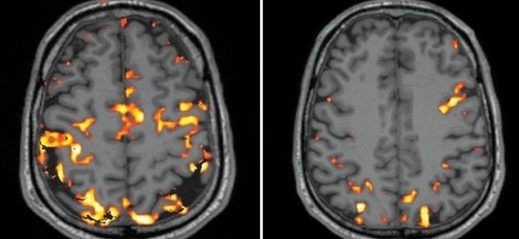

çocuğun beyin gelişimi. çocuğun zeka geli̇şi̇mi̇ i̇çi̇n neler yapilmali. Ancak şunu hatırlatalım araştırmayı yapan doktor iki çocuğun beynini karşılaştırmış. çocuğumuzun yaşantısı beynin yapısını etkiliyor ve kimliğini tanımlıyor. Yaşanan olumlu ya da olumsuz deneyimler bir çocuğun gelişimini etkileyebilir ve bu etkiler yaşam boyu devam edebilir.

Doğumdan sonra beyin çocuğun toplam ağırlığının yaklaşık olarak dörtte biri kadardır. Konu ile ilgili araştırma gösteriyor ki ilgiden sevgiden mahrum yetişen ailesiyle zaman geçirmeyen çocuklarda beyin gelişimi normalin gerisinde oluyor ve beyin daha küçük kalıyor. Yetersizliği çocuğun bilişsel motor ve sosyo duygusal becerilerinin gelişimini olumsuz etkilemekte bu da. Beyin gelişiminin 80 i bu dönemde tamamlanır ve beyin ölçüsü neredeyse yetişkinlikteki büyüklüğe ulaşır.